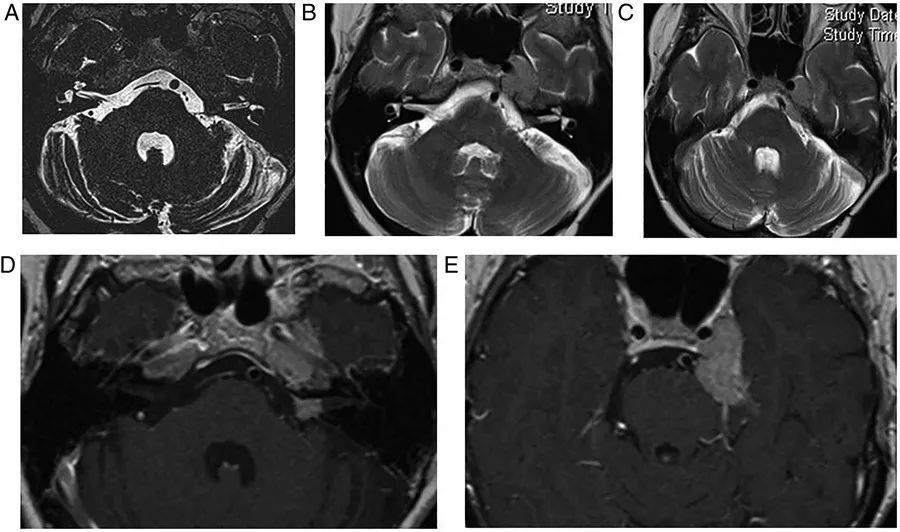

图2  肺部原发肿瘤转移。左侧桥小脑区可见转移灶,当桥小脑区结构不清时,有时很难区别是轴内病变还是轴外病变。这种不均匀的强化提示转移瘤,小脑无水肿则提示轴外病变

图3  结核瘤。左侧小脑表面可见一环形强化的结核瘤,膨胀进入桥小脑角区,并呈现出类似于轴外病变的外观,不过由于存在小脑水肿,该病灶更可能源于轴内。此外,右侧外侧裂可见脑膜强化,即脑膜炎的证据